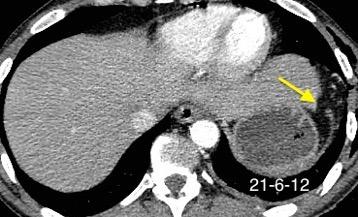

Recibe una puñalada en costado izquierdo

La laceración tiende a ocurrir en la unión

músculotendinosa . (64-90% en el lado izquierdo)

Diafragma “colgante” (“dangling sign”)

(“Dangling sign”)

TC. Mejor con multicorte. (reconstrucciones).

Asociación: Aire en pared.

Fracturas costal .Rotura esplénica. Neumoperitoneo.

Diafragma discontinúo Herniación de la grasa omental

Desser TS et al.The dangling diaphragm sign: sensitivity and comparison with existing CT signs of blunt traumatic diaphragmatic rupture. Emerg Radiol 2010